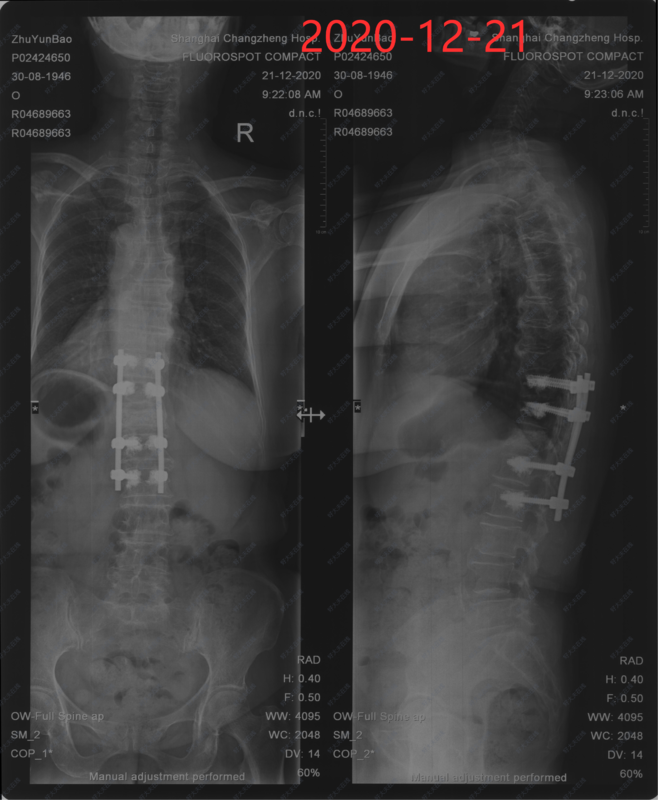

- 治疗后90天

术后3月左右患者来门诊随访。腰背部疼痛完全消失,双下肢活动良好,自行步入病室,步态稳定,患者自觉恢复良好。复查X线提示内固定位置良好,胸腰椎后凸畸形恢复良好。